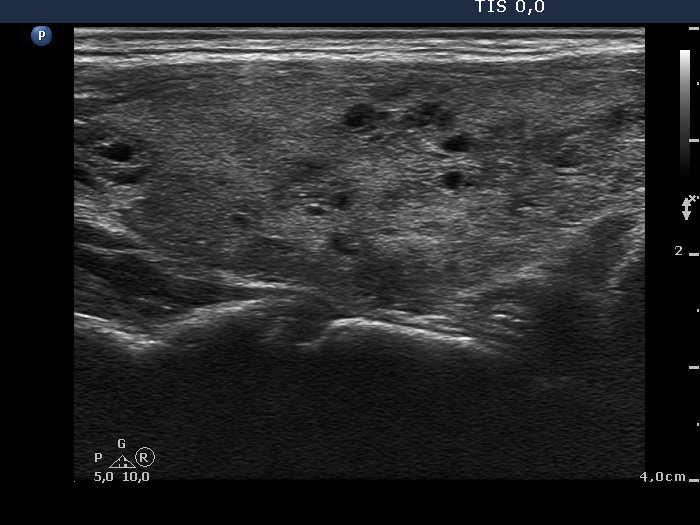

Consecutively operated patients with autoimmune thyroid disease - case 18 (1741) (ultrasonographic picture 6)

Upper part of the left lobe, longitudinal view.